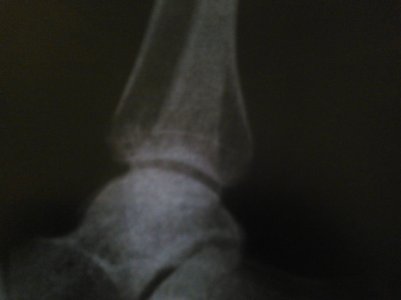

Отдельно прилагаются фото МРТ, КТ, рентгенография.